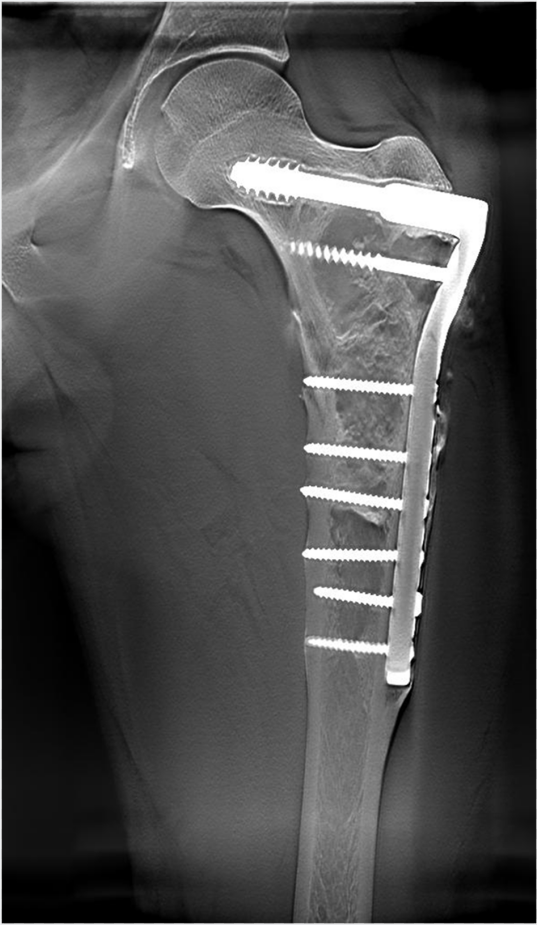

提高了金属植入物周围结构的显示能力(图4)

dr数字怎么用数字化X线摄影术(DR)_https://www.jmylbn.com_新闻资讯_第6张

图4  股骨金属植入物术后DTS

DTS检查股骨颈及股骨上段见金属内固定影,骨皮质及髓腔病理改变显示清晰